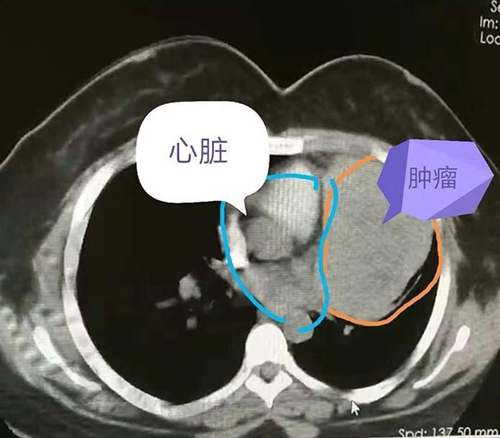

女孩今年8月份参加单位的体检,发现胸部有肿块,医院医生让她做了一个胸部CT检查,结果发现纵隔长了一个肿瘤,诊断为胸腺瘤。

可是,女孩没有想到的是,肿瘤的生长超出预期,最近两周突然出现睁不开眼的情况。再次就医,医生告诉她,这应该是胸腺瘤生长造成的重症肌无力。再次检查,发现肿瘤较8月份明显长大, 同时发现肿瘤压迫了心脏大血管和肺组织。

从手术本身来考虑,这个手术风险很高,一是在肿瘤切除的时候可能造成大出血,下不了台;另一方面,由于肿瘤和周围脏器生长密切,不一定能完整切除。

手术中发现肿瘤侵犯了肺动脉外膜,对肺也有侵犯,经过2个多小时的仔细剥离,终于完整切除了肿瘤,同时,还切除了部分心包和受侵犯的肺组织。